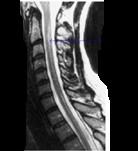

问题 患者,女性,60岁,既往有萎缩性胃炎。因双下肢无力、行走不稳3月来诊。表现精神不振,轻度贫血,双下肢不完全痉挛瘫痪,振动觉、位置觉障碍,行颈髓MRIT项出现如图所示病变。最可能的诊断是 ( )

选项 A、急性脊髓灰质炎 B、脊髓压迫症 C、急性脊髓炎 D、脊髓亚急性联合变性 E、重症肌无力 一、单项选择题

答案 D